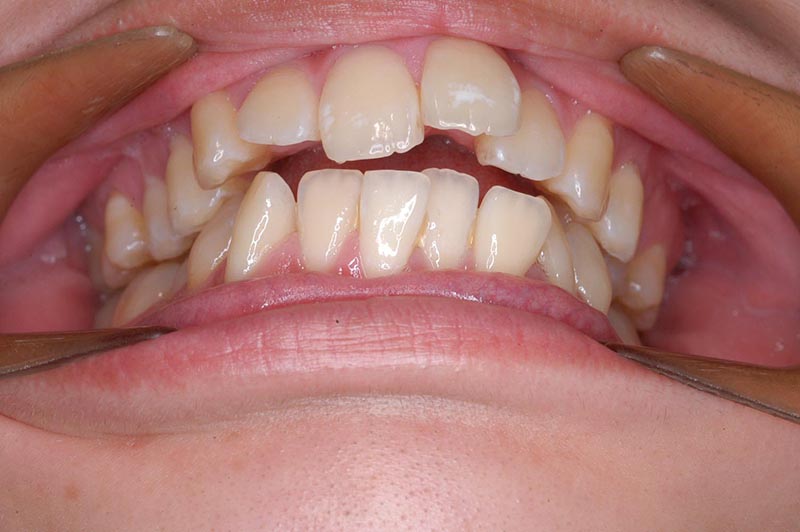

主訴 口が閉じづらい 診断名 アングルⅠ級上下顎前突症例

初診時年齢 19歳5ヵ月 性別 動的治療期間 26ヵ月

口腔内所見 大臼歯関係はⅠ級。顔面正中に対して上顎正中は一致しており、下顎正中は右側に偏位していた。上下顎前歯は大きく唇側傾斜し、overjetが7.8mmの上突咬合、両突歯列、叢生歯列弓であった。